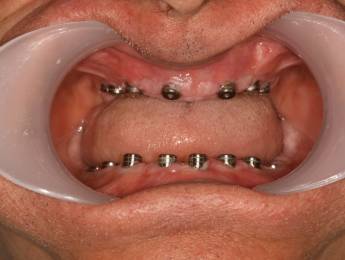

FOGBEÜLTETÉS TELJES FOGATLANSÁG ESETÉN

A legjobb megoldás, amikor 6-8 implantátumot az állcsontba ültetve egy fix híd készülhet a fogsor helyére.

Ideális esetben 8 implantátumra készülhet a 12 fogat pótló híd, mely teljesen rögzített a szájban. A páciens ezt nem tudja eltávolítani.

Ha a páciens már régen elvesztette a fogait az az eset állhat elő, hogy a csontfelszívódás miatt már nem lehet fix megoldást készíteni, mert az állkapocs elülső részén is felszívódott a csont. Ebben az esetben 2-3-4 implantátum beültetése után ezekre az implantátumokra egy speciálisan készített fogsort, az úgynevezett overdenture-t lehet rögzíteni.

Ennél a megoldásnál egy fix csavarozott stég kerül az implantátumokra, erre rögzül a fogsor, mely jellegében a hagyományos műfogsorra hasonlít, de az implantátum miatt annál sokkal stabilabb, és egyáltalán nem mozog. Ezenkívül az implantátumok itt is stimulálják a csontot, tehát megáll a csont sorvadása.